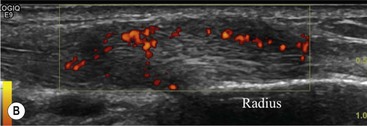

The affected tendon is thickened and hyporeflective on US, with neovascularisation on Doppler imaging (Fig. 46-16). High SI is demonstrated on fluid-sensitive MRI sequences (Fig. 46-17). Tendon tears are demonstrated as focal areas of deficiency.13 In chronic cases, new bone formation may be seen on radiographs at the tendon enthesis. Calcific tendinopathy is much less common than in the rotator cuff of the shoulder.